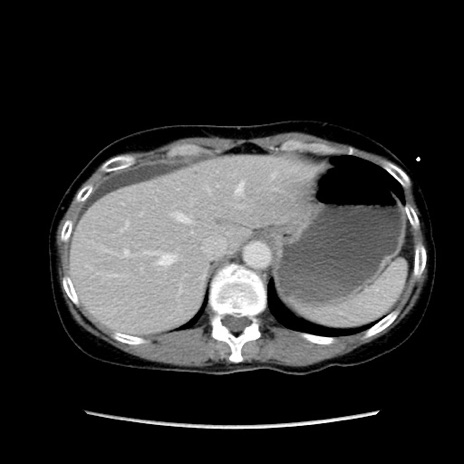

矢状断像

【症例】40歳代 女性

【主訴】上腹部痛、嘔気・嘔吐

【現病歴】約9時間前頃から急に上腹部痛、嘔気、嘔吐が出現。改善しないため救急要請。

【既往歴】子宮頚癌(広汎子宮全摘術、放射線療法)、腸閉塞

【身体所見】腹部:平坦、軟、腸雑音亢進、上腹部を中心に腹部全体に圧痛あり。

【データ】WBC 8400、CRP 0.03